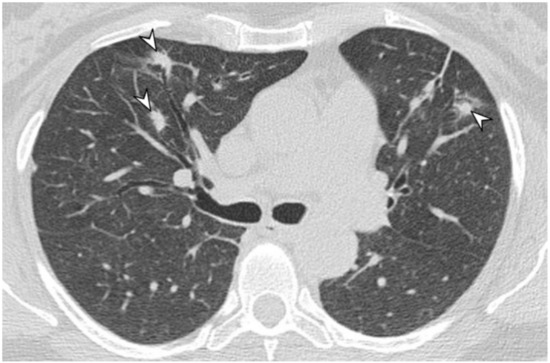

2.3. Microscopic Polyangiitis (MPA)

| MPA | GGOs due to hemorrhagic alveolitis (common); consolidation, nodules with centrilobular distribution (less common) |